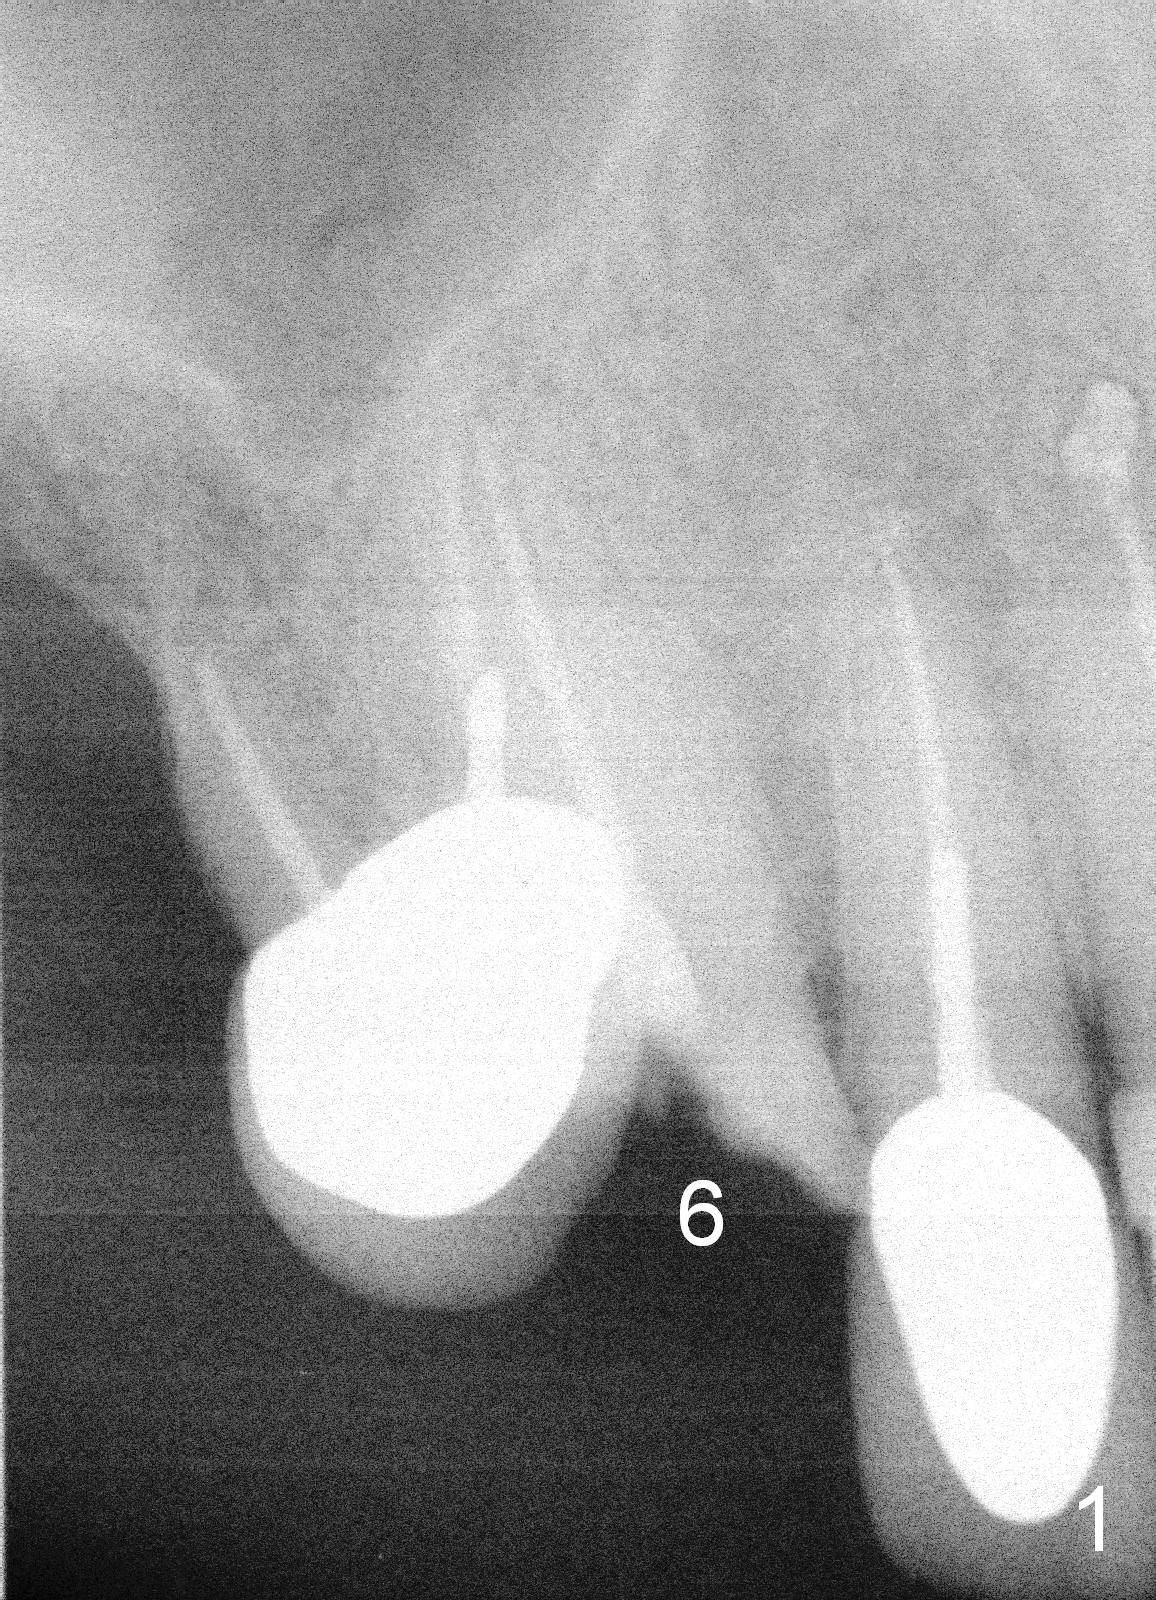

The tooth #6 of a 70-year-old man (TF) fractures subgingival (Fig.1) before final upper left implant restorations. A 15 mm or longer UF implant (Fig.2) seems to be appropriate for the site immediately after extraction (socket treated with Clindamycin).